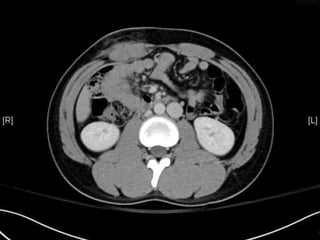

• CT:

 Shanmuganathan(2004)

 Sen:97%, spe:98%, accuracy:98% in penetrating stab wds

 Velmahos(2005)

 GSW: Sen 90.5, Spe: 96%

Radiology 2004:231:775-784

J trauma 2005:59:1155-1161